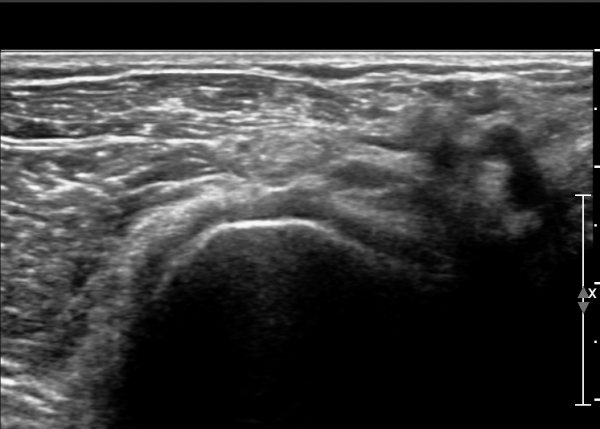

¿ä°ñ ¸ñ ºÎÀ§¿¡¼­ Èİñ°£½Å°æ Ⱦ´Ü¸é°Ë»ç»ó Èİñ°£½Å°æÀÇ Àú¿¡ÄÚ ºÎÁ¾ÀÌ °üÂûµÈ´Ù(»çÁø 2).